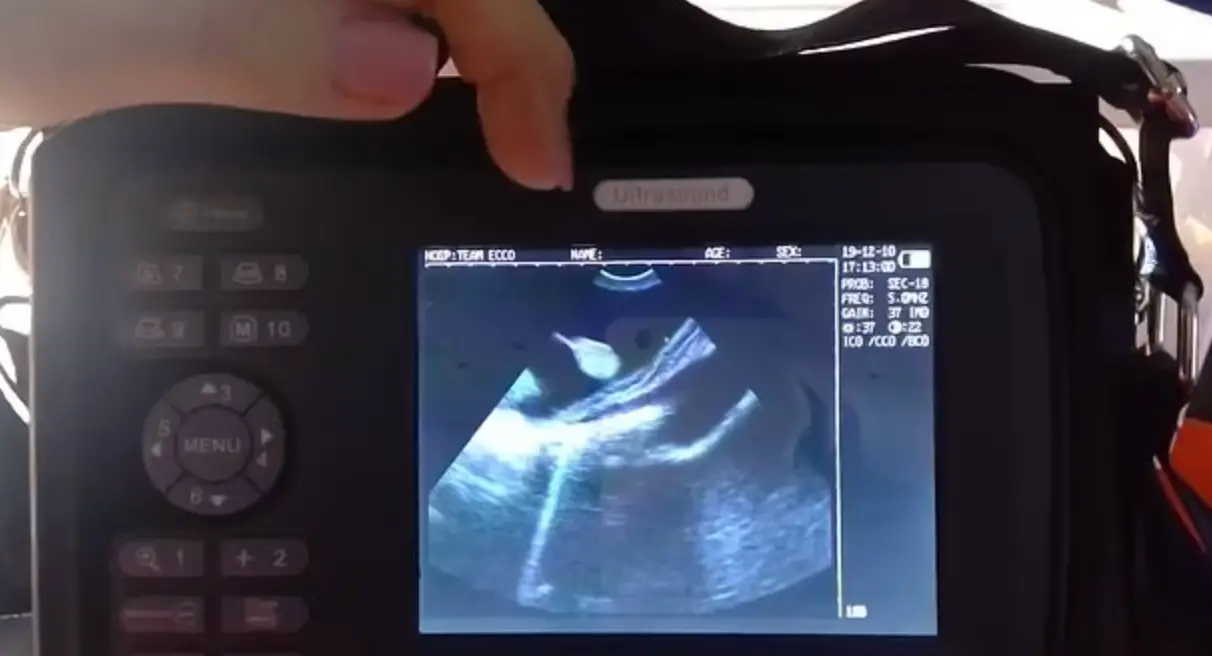

Staff at The Aquarium and Shark Lab in North Carolina were initially concerned that Charlotte the stingray had cancer after they noticed some swelling back in September and decided to carry out an ultrasound.

A staff member said: “We have been doing ultrasound on our ray, Charlotte, since September, when she began to swell. We documented multiple 'growths' internally and initially thought she had a cancer.

“I reached out to Dr. Rob Jones, the aquarium vet, and he identified the growths as eggs. We have no male ray. He said there have been few cases of parthenogenesis in rays.”